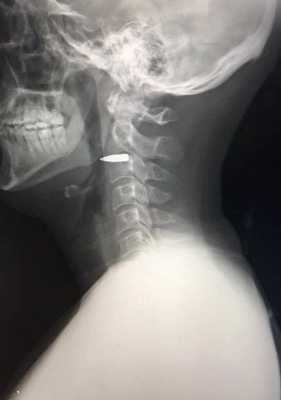

На основании диагноза определены показания к срочной ревизии и первичной хирургической обработке раны. Протокол хирургического вмешательства: в связи с невозможностью оротрахеальной интубации операция выполнена под внутренней анестезией. Выявлено полное пересечение мышц надподъязычной группы непосредственно выше подъязычной кости; отмечается зияющий дефект глотки, через который видна ее задняя стенка, подъязычная кость вместе с гортанью смещена вниз, язык отсечен от основания и западает кзади, что вызывает нарушения дыхания и создает угрозу асфиксии, препятствует выполнению оротрахеальной интубации. Расхождение краев раны составляет 1,5—2 см. В ране отмечается выраженное кровотечение и скопление слюны. Источником массивного кровотечения является пересеченная правая верхнещитовидная артерия. Поврежденная артерия взята на зажим, а затем перевязана. Подъязычная кость и надгортанник взяты на зажимы, гортань подтянута кверху, после чего проведена временная интубация трахеи через рану. Через дополнительный разрез на уровне второго—третьего колец трахеи наложена трахеостома, после чего в трахею введена интубационная трубка с манжетой (рис. 1). Рис. 1. Больной С. Интубация трахеи через наложенную трахеостому. Из глотки и полости рта удалено большое количество крови и сгустков, после чего введен назогастральный зонд. Визуализируются три резаные раны корня языка, которые были последовательно ушиты. Выявлено повреждение правой подчелюстной железы, а в латеральном углу раны определяется наружная сонная артерия (рис. 2). Рис. 2. Первичная хирургическая обработка раны. Описание в тексте.